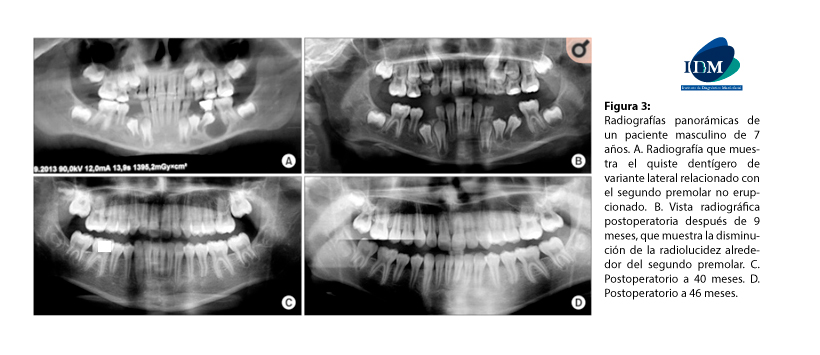

Figura 3: Radiografías panorámicas de un paciente masculino de 7 años. A. Radiografía que muestra el quiste dentígero de variante lateral relacionado con el segundo premolar no erupcionado. B. Vista radiográfica postoperatoria después de 9 meses, que muestra la disminución de la radiolucidez alrededor del segundo premolar. C. Postoperatorio a 40 meses. D. Postoperatorio a 46 meses.